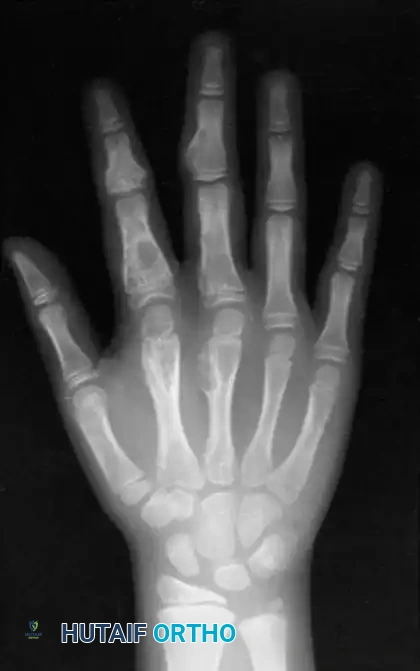

Giant Cell Tumor of the Tendon Sheath (Xanthoma)

Giant cell tumors of the tendon sheath (GCTTS) are the second most common solid cellular tumors of the hand. They occur most frequently between the ages of 8 and 80 years and exhibit a strong predilection for the palmar aspect of the digits. Multiple xanthomas may be indicative of underlying hypercholesterolemia.

Clinical and Histological Profile

GCTTS are typically slow-growing, painless masses. However, when located adjacent to a joint (most commonly the proximal interphalangeal joint), they can mechanically block flexion or extension. Grossly, they appear as yellow or tan lobulated masses. Histologically, they are composed of spindle cells, fibrous tissue, cholesterol-laden histiocytes, multinucleated giant cells, and hemosiderin deposits.

Surgical Excision and Recurrence

Excision is notoriously difficult. These tumors frequently wind in and around the flexor tendons, their synovial sheaths, digital nerves, and occasionally the extensor mechanism, sometimes encompassing three-fourths of

Associated Surgical & Radiographic Imaging

Hutaifortho's Orthopaedic Diagram